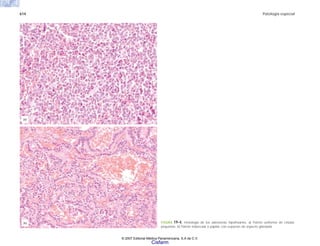

FIGURA 2-7. Mieloma múltiple. a) Histología de la neoplasia. b) Citología de un

frotis del tumor, que permite apreciar la morfología de las células plasmáticas

neoplásicas. (Cortesía del Dr. Joaquín Carrillo.)